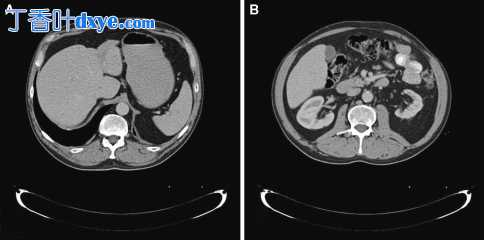

腹部超声检查显示肝肿大,肝内胆管扩张,无胆石症、胰腺或肝门肿瘤征象。腹部 CT 显示肝肿大,两个肝叶都有明显的胆汁淤积,胆囊壁增厚,主动脉腹侧有 5 毫米厚的软组织套,反映了奥蒙德病过程中的硬化变化(图 1a,b)。

图 1

CT显示肝肿大伴胆汁淤积,肝叶(a)和主动脉腹侧软组织套(b)